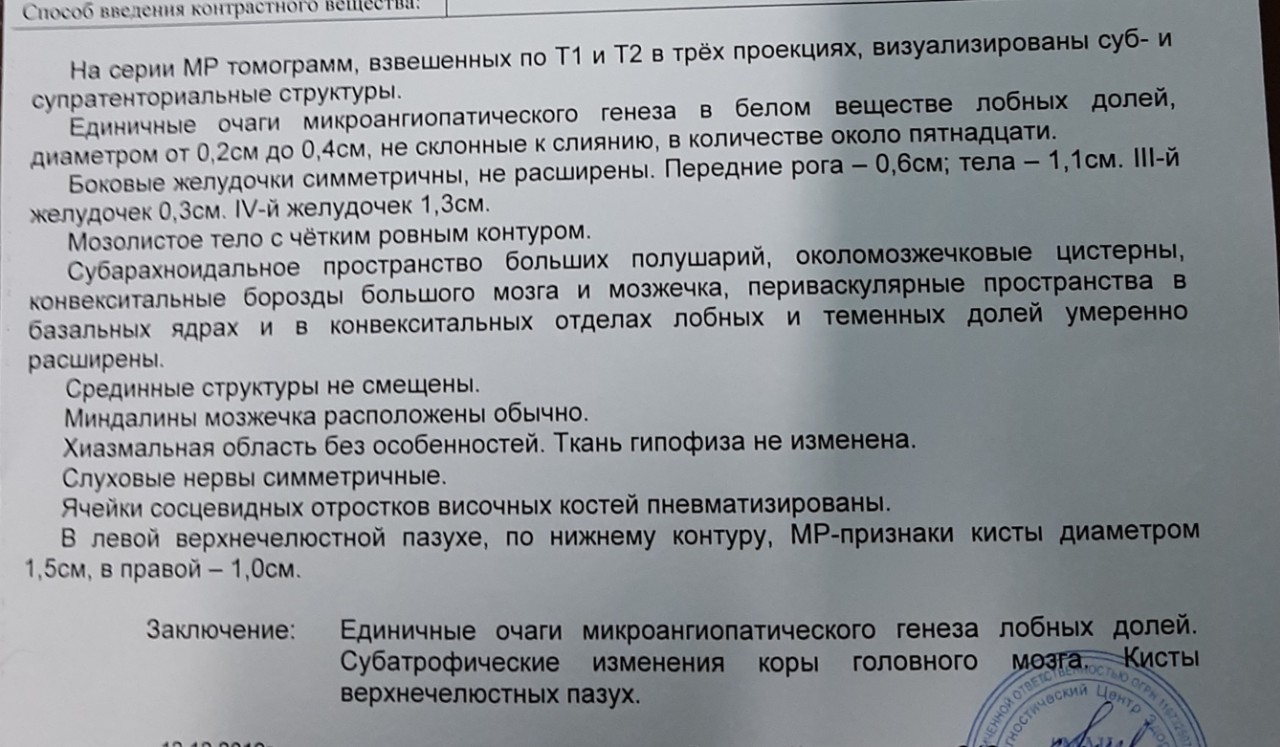

Демиелинизирующие заболевания мозга: МРТ изображения

Раздел: Путеводитель по жизни